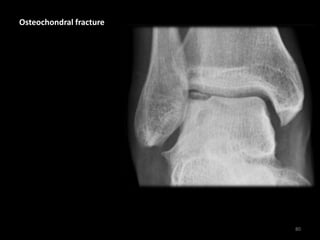

Osteochondral fracture

80

Loss of the normal talar

dome cortex contour due

to an osteochondral

fracture